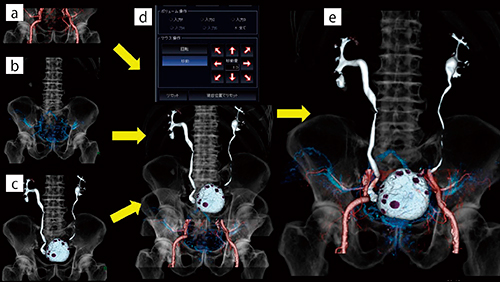

そこで現在は,ある程度尿をためた状態で通常の造影撮影を実施し,次の患者の検査を行った後に再入室してもらい,排泄相のみの追加撮影を行っている。これにより注入時間のロスは軽減し,膀胱内の造影剤が歩行により尿と均一に混ざることによって,病変部の位置に関係なく常に背臥位で撮影を行うことができる(図1 b)。また,膀胱のレイヤー抽出においても,オパシティカーブの調整のみと格段に容易になった(図1 d)。本法は患者が一度退室するため,画像処理において早期相(図2 a),遅延相(図2 b),排泄相(図2 c)の寝台位置が一致しない(図2 d)。そこで,各フェーズの骨のレイヤーをマルチボリューム処理上でメルクマールとし,マニュアルのボリューム操作で位置合わせを行っている。これにより,患者やわれわれ診療放射線技師の負担を軽減しながらも,オリーブオイル以上の効果を得ることが可能となった(図2 e)。

図2 膀胱腫瘍におけるマルチボリューム処理の手順

a:早期相VR画像 b:遅延相VR画像 c:排泄相VR画像

d:寝台位置でリセットした早期相,遅延相,排泄相のマルチボリューム処理VR画像。排泄相にズレが生じている。

e:各フェーズの骨のレイヤーをメルクマールとしてマニュアルのボリューム操作で位置合わせを行ったVR画像